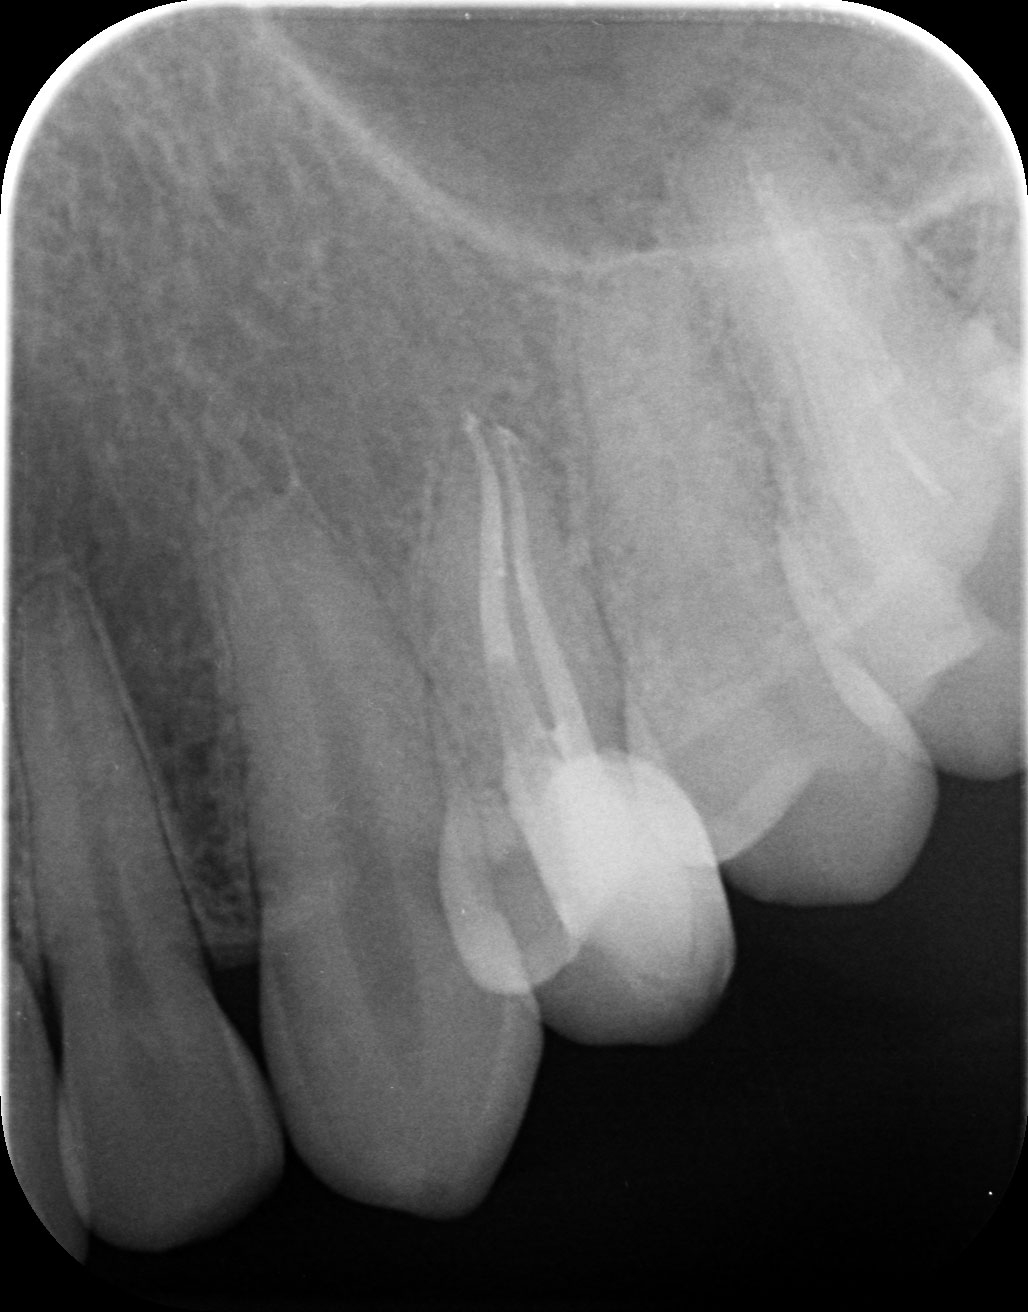

Dantų kanalų gydymas